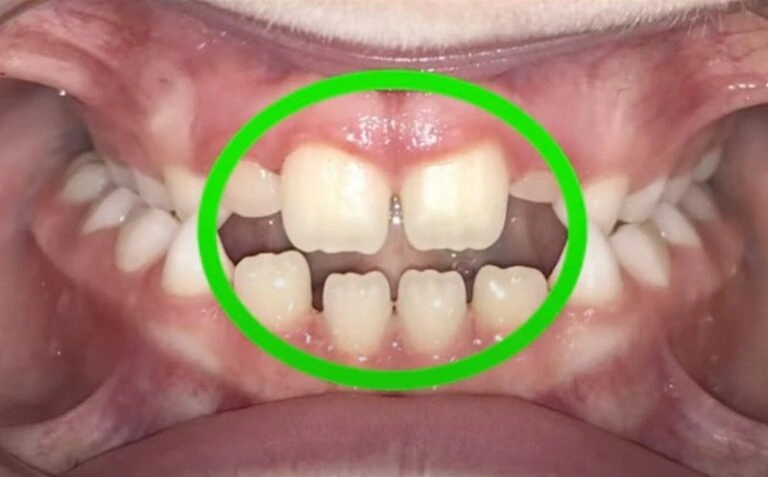

3. Crowding Issues

This is one of the most common reasons I see, and it’s something we should address early! If there isn’t enough space in your child’s mouth for their adult teeth to come in, the baby tooth can get stuck in place. As a result, the adult tooth might grow in behind or on top of the baby tooth, making things even more complicated.